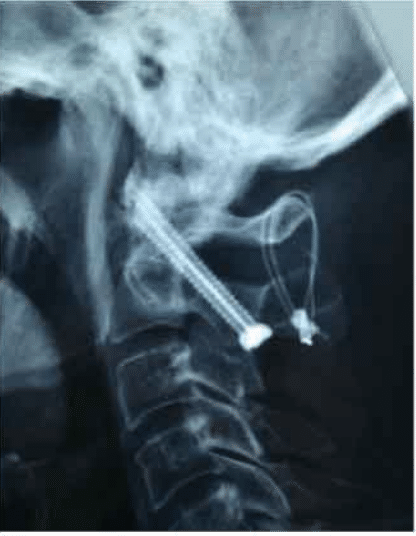

C1-C2 was reducible on extension and held in position on the operating table. Laminectomy was not required in this situation.

C1-C2 was maintained in extension with C1-C2 trans articular screw fixation with additional wiring of the posterior arch of C1 to C2 and bone grafting was done.